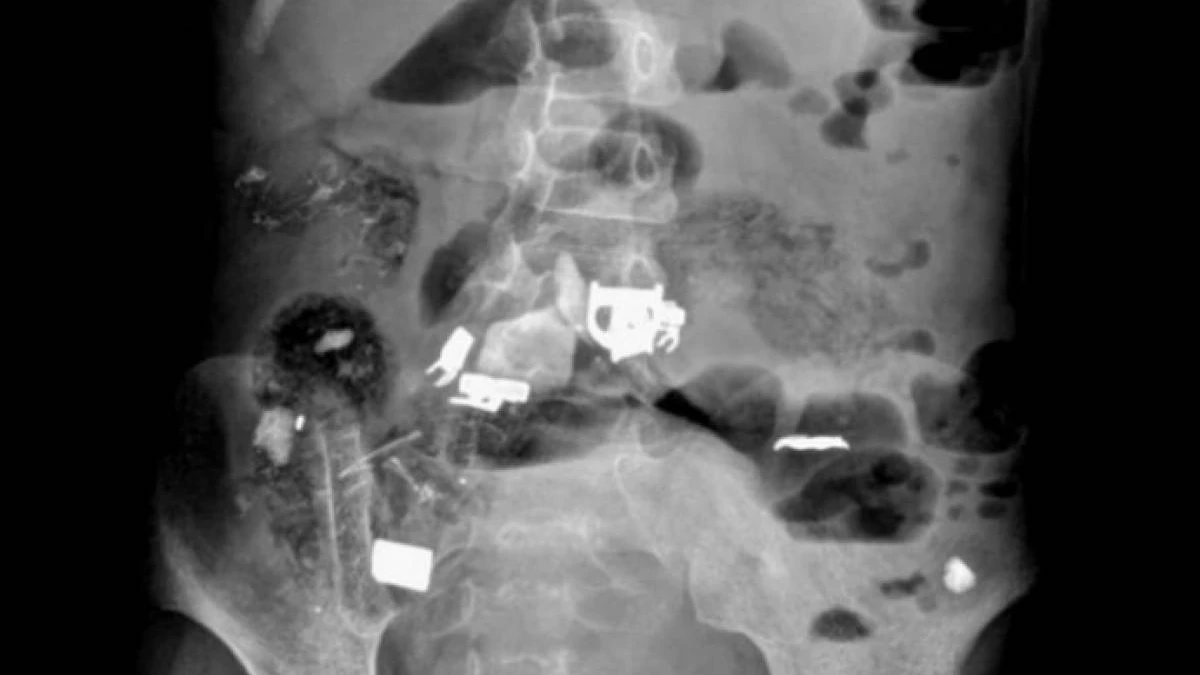

"Ақпан айында облыстық балалар ауруханасында Жаңөзен қаласында тұратын 12 жасар мүгедек балаға шұғыл түрде ота жасалды. Бұл бала (12 жастағы қыз бала) ауруханаға іштің түйіліп ауруы және өте көп мөлшерде құсу шағымымен түсті. Құрсақ қуысы органдарын рентгенге түсіру нәтижесінде, баланың ішінде бөтен заттардың жатқандығы анықталды", - делінген хабарламада.

Дәрігерлердің жедел іс-әрекетінің арқасында, ота барысында қыз баланың ішегінен бөтен заттар (темір, қалам, скотч, шаш) шығарылды.